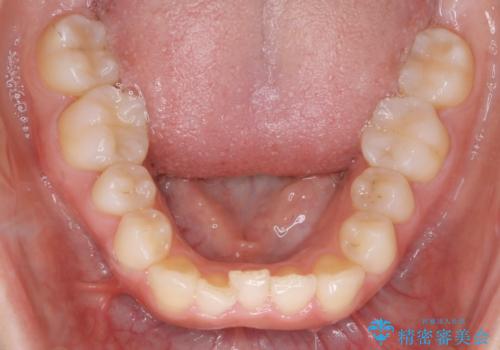

下顎については、前歯にがたつきがありました。

下顎については、歯の側面を削ることをメインにがたつきを改善しました。